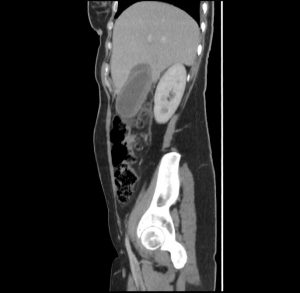

Five days after the operative treatment, the patient experienced severe abdominal pain accompanied by nausea and vomiting. The laboratory results showed elevated white cells count 11.1 (normal range: 4.00-9.00 10/9L), elevated CRP 67.3 (normal range: under 6mg/L), normal total bilirubin 14 (normal range under 20.5umol/L) and elevated direct bilirubin 10.2 (normal range: under 6.8umol/L). Control CT scan of the abdomen with intravenous contrast was performed, where in the region of the gall bladder a dense free liquid collection was observed, around which small free air inclusions were present, the clips of the cystic artery and ductus cysticus were also visible, and a smaller amount of free liquid was present in the pelvis.

An MRCP was performed next, that showed intact common bile duct and intact cystic duct stump. Also, an area of fluid accumulation was noted in the subhepatic space, intraintestinal and in the small pelvis. Subcutaneous oedema in the right lateral abdominal wall was also noted, most likely post operatively.